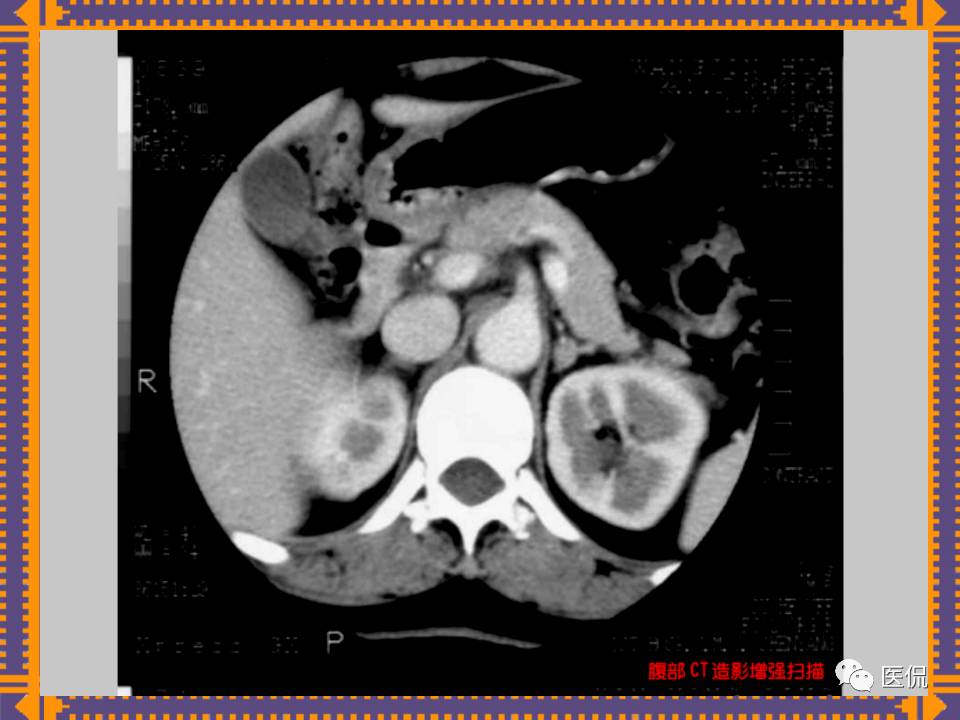

这篇PPT对男性生殖系统疾病:前列腺增生、前列腺癌;女性生殖系统疾病:子宫肌瘤、子宫癌、卵巢囊肿和卵巢肿瘤以及腹膜后间隙疾病进行了详细讲解。